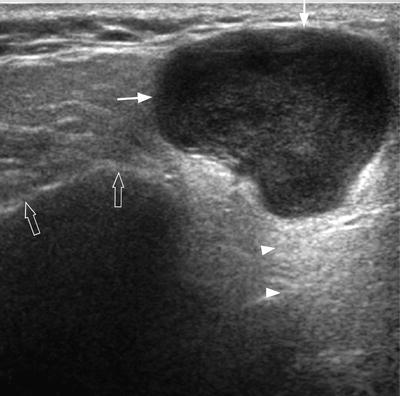

Head and neck cancers include cancers in: There can be more than one sentinel node. I had an ultrasound done in 2012 but the report for this scan never reached my previous doctor's practice and so nothing was. This study was done to evaluate the use of ultrasound to examine lymph nodes in the neck in surgical planning for thyroid cancer surgery and to identify which patients are best served. An ultrasound of the thyroid produces pictures of the thyroid gland and the adjacent structures in the neck. While it can't diagnose cancer, it can detect the abnormal tissues that may possibly be cancerous. The image may or may not suggest cancer, but definitive diagnosis requires removal of. For most types of cancer, a biopsy is the only sure way for the doctor to know if an area of the body has cancer. When ultrasound is performed on a patient with nodular goiter, or a patient with a history of thyroid cancer, finding a prominent lymph node with a rounded shape (long/short axis ratio < 2) and absent hilar line warrants further evaluation of the node (figs. Ultrasounds have many limitations an ultrasound is not good enough for many aspects of cancer. Carotid ultrasound tests for blocked or narrowed carotid arteries, which can increase the. Confirming that a lump in the neck is developing from the thyroid or connected tissue. Spread of thyroid cancer to the lymph nodes in the neck is common and increases the risk of cancer recurrence.

Figure 3 From Post Thyroidectomy Neck Ultrasonography In Patients With Thyroid Cancer And A Review Of The Literature Semantic Scholar from d3i71xaburhd42.cloudfront.net Ultrasound is often one of the first line tests in the detection of cancer. These tests can also show whether a nodule is toxic or producing too much thyroxine, causing hyperthyroidism. Spread of thyroid cancer to the lymph nodes in the neck is common and increases the risk of cancer recurrence. I was officially diagnosed hashimoto's by my endocrinologist 2 weeks ago but she has refused to do an ultrasound of the thyroid. 8.4, 8.5, 8.6, 8.7, and 8.8). An ultrasound of the neck is used to examine the carotid arteries located on each side of a patient's neck. Our doctors also use ultrasound to check lymph nodes in the neck, where some forms of thyroid cancer can spread. It can be used with a fine needle aspiration test or core biopsy test to accurately direct the tip of the needle into the lump.

Carotid ultrasound tests for blocked or narrowed carotid arteries, which can increase the. Some of the indications for thyroid or neck ultrasound are thyroid nodules, goiter, thyroid cancer and other neck masses. Expert ultrasound can also help confirm a diagnosis of papillary thyroid cancer which has spread to the lymph nodes of the neck. It can detect abnormal tissues, growths, and cysts and give a suspicion of cancer based on how those images look. Ultrasound is widely available an is useful to identify abnormal lymph nodes that may contain cancer.

People may use the word throat to describe different parts of the neck. Your two carotid arteries are located on each side of your neck. A neck ultrasound can be used to observe the thyroid gland to look for nodules, growths, or tumors. Although many unskilled observers would believe that size is a major issue, but it actually is not. Lymph nodes are part of the lymphatic system, which helps to protect us from infection and disease. If this happens, it is called metastasis. Part of the throat (cancers of the oropharynx and tonsils, nasopharynx and hypopharynx) the nose or sinuses (nasal and sinus cancer) the salivary glands. If the person has a lump in the neck, an fna can show if the mass is from cancer spread. The expert ultrasonographer will look for multiple changes. While it can't diagnose cancer, it can detect the abnormal tissues that may possibly be cancerous. Ultrasound guidance is used to perform thyroid biopsies and improves the diagnostic accuracy of fine needle biopsy. If this lump is of concern then a biopsy would be the next step. An ultrasound of the neck is used to examine the carotid arteries located on each side of a patient's neck.